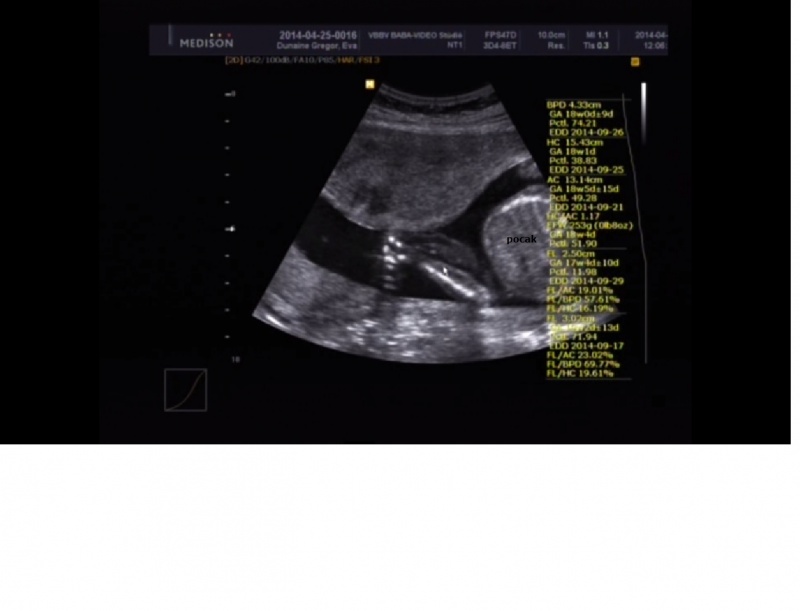

Hasfal: Ép hasfal és köldökzsinór eredés. A köldökzsinór három eret tartalmaz.

Hasüreg: gyomortelődés kimutatható, a máj és a belek echogenítása szabályos.

Vesék: helyzete, alakja, szerkezete és mérete mindkét oldalon phyziológiás, normális tágasságú üregrendszerrel. Jó hólyagtelítődés.

Végtagok hosszú csöves csontjai hiánytalanul ábrázolódnak. Kezek és lábfejek megjelenése normális, durva rendellenesség jelenleg nem látható. Körülírt kóros folyadékgyülem a testüregekben nem észlelhető. Subcutan oedema nem látszik.